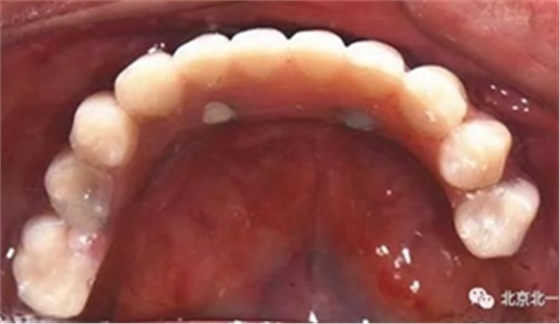

圖十八:口內(nèi)試戴鈦支架

圖二十五:口內(nèi)照。